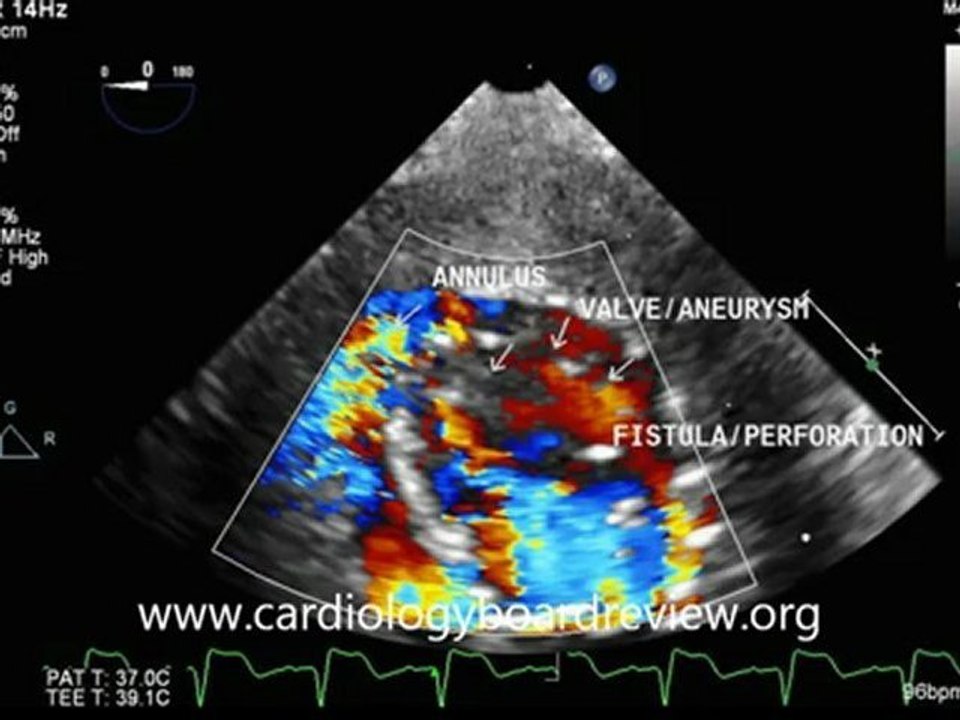

Posterior Mitral Valve Leaflet Aneurysm 2:33

Posterior Mitral Valve Leaflet Aneurysm

cardiologyboardreview 1 views